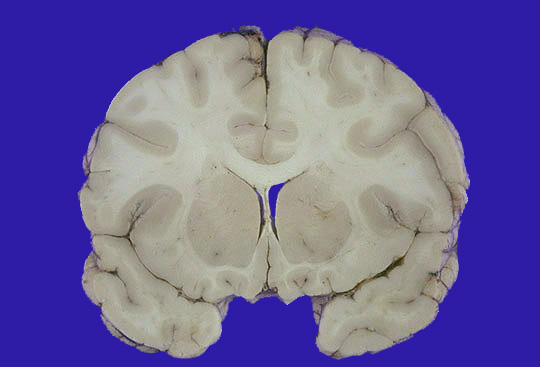

A head CT scan is performed. The findings are those represented by the gross appearance shown here [Image courtesty of Jeannette J. Townsend MD, University of Utah]

Figure 2: Head CT scan